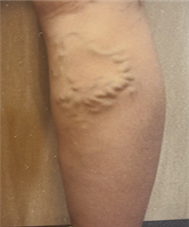

혈관은 아래의 사진들처럼,

아주 얇고 가는 실핏줄부터 지렁이 굵기의 튀어나온 혈관까지

다양한 모양으로 보일 수 있습니다.

특히나 혈관이 구불구불한 모양으로 많이 튀어나와보어거나,

다리의 쥐, 무거움, 통증 등의 증상을 동반한다면

다리가 보내는 하지정맥류의 신호일 수 있습니다.